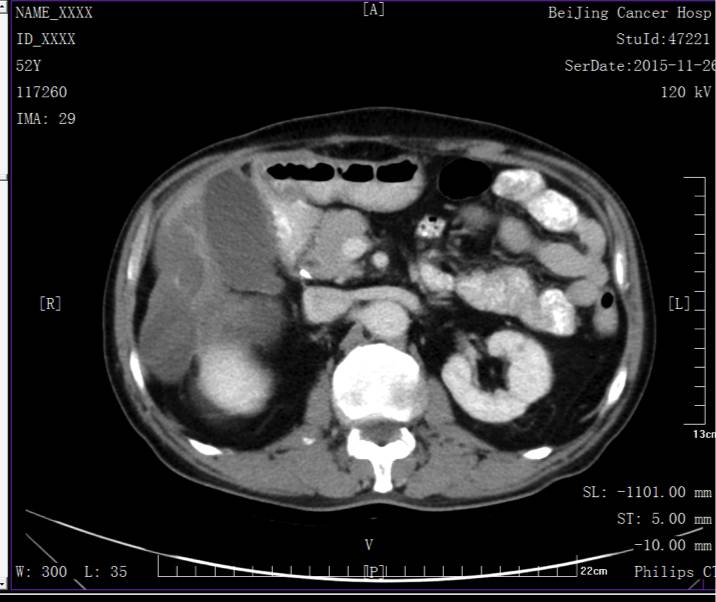

定期复查未见复发转移。

末次复查日期2015.11.18。腹盆部CT、胸片未见异常。